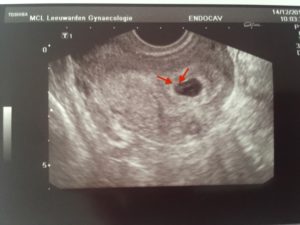

Нормальными показателями размеров зародыша принято считать:

- Внутренний диаметр плода равен 18–22 мм.

- Копчико-теменной размер зародыша достигает 3–6 мм. Данные актуальны на 28 день после подсаживания клетки.

- Желточный мешочек должен равняться 3 мм в диаметре.

Сведения не дают на 100% корректную картину, поскольку зависят от дня имплантации эмбриона. Обычно для наступления беременности необходимо 3–10 дней, в зависимости от подготовки среды в матке на день переноса зародышей. Сроки внедрения эмбрионов в матку еще зависят от дня продолжительности жизни бластоцисты. Обычно пятидневки быстрее имплантируют, чем трехдневки.